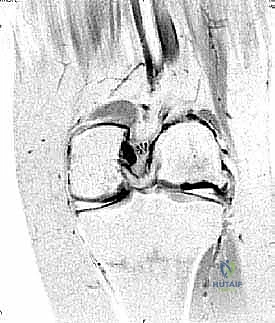

- Patient Selection & Lesion Assessment: This procedure is ideally suited for osteochondral lesions up to 10 mm in diameter and 10 mm deep, located in the anterior two-thirds of the medial or lateral talar dome margins. We've already reviewed our patient's MRI and CT scans, confirming the lesion's size, depth, and exact location. This helps us anticipate the required exposure and graft size.

- Osteology: We're operating around the distal tibia, specifically the tibial plafond, and the talus. The medial malleolus forms the medial wall of the ankle mortise. The angle of Hardy is a key anatomical landmark, representing the anterior-most extent of the medial malleolar facet, which guides our osteotomy. The talar dome, our target, articulates with the tibial plafond.